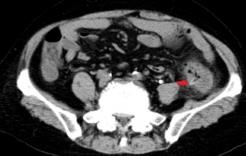

急诊外科陈峰主任接到会诊通知后,率先赶到了现场,结合患者病史、查体以及辅助检查,考虑“消化道穿孔”,手术指征是明确的,但是“拦路虎”也摆在面前,高龄的张阿婆不仅存在慢性肾功能不全、支气管哮喘、血小板增多症、高血压、糖尿病等多种疾病,既往有“肺栓塞”病史的她长期口服抗凝药物华法林,无论是术中,还是术后都存在腹腔出血以及脏器功能衰竭的风险。在与患者家属充分沟通后,急诊外科团队顶着巨大的压力为张阿婆开展了急诊手术。

完善术前准备后,随后的手术立即紧张有序展开,陈峰主任术中探查发现一枚尖尖的枣核扎穿了结肠,仍有粪液不断流出,手术组迅速取出了枣核并进行了肠造瘘。术后经过一系列治疗后,老人顺利渡过了危险期,现在已基本康复准备出院。